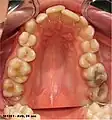

Face antérieure

La partie postérieure (segment pharyngien) de la face antérieure de la langue comprend l'épiglotte, les amygdales linguales, les piliers antérieurs et postérieurs entre lesquels logent l'amygdale palatine et le foramen cæcum. La portion pharyngienne de la langue est peu visible normalement lorsque la bouche est ouverte. Cette partie va jusqu'au sillon terminal de la langue, là où commence la langue comme elle est définie par la majorité des gens, soit la section buccale de la langue.

La section buccale part de l'apex de la langue jusqu'au sillon terminal et est parcourue par un sillon médian. C'est sur cette partie que se trouvent les papilles.

Papilles gustatives

Chez l'humain, les papilles gustatives permettent de reconnaître les différentes saveurs : sucré, salé, amer, l'umami et l'acide. Des papilles gustatives recouvrent la langue et sont responsables de la perception des goûts. Les papilles se classent en quatre sortes :

- les papilles circumvallées (ou caliciformes), au nombre de 12, formant le V lingual qui délimite les 2/3 antérieur du 1/3 postérieur de la langue ;

- les papilles fongiformes, disséminées sur la pointe et les 2/3 antérieur de la langue ;

- les papilles filiformes, celles qui sont présentes en plus grand nombre et donnent à la langue sa texture particulière et situées de part et d'autre du sillon médian ;

- les papilles foliées (ou coralliformes), situées sur les bords latéraux et postérieurs de la langue.